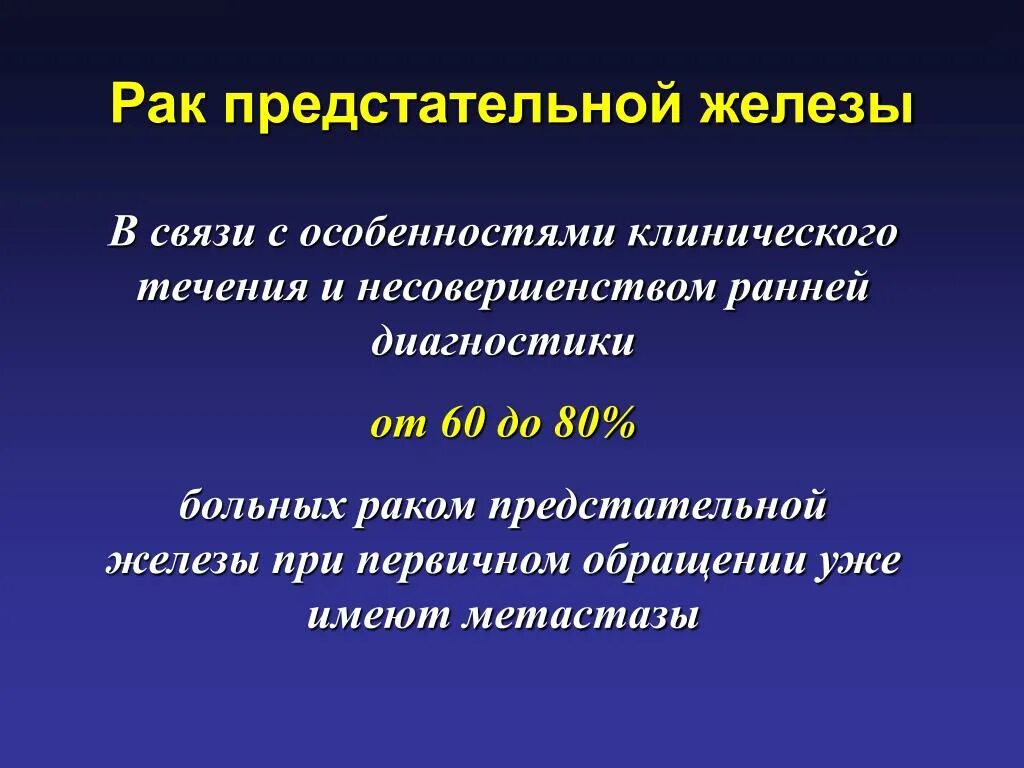

Опухоль предстательной железы. Карцинома предстательной железы. Опухоль предстательной железы презентация. Онкология предстательной железы

Опухоль предстательной железы. Карцинома предстательной железы. Опухоль предстательной железы презентация. Онкология предстательной железы Опухоль предстательной железы. Злокачественная опухоль предстательной железы. Карцинома предстательной железы. Предстательная железа развивается из

Онкология предстательной железы. Опухоль простаты симптомы. Карцинома предстательной железы Онкология предстательной железы. Предстательная железа презентация. Презентация онкология предстательной. Предстательная железа rak

Онкология предстательной железы. Предстательная железа презентация. Презентация онкология предстательной. Предстательная железа rak Предстательная железа в пожилом возрасте. Простатит 3 степени 2 класс. Метастазы простата рисунок

Предстательная железа фото Онкология предстательной железы. Степени опухолей простаты. Предстательная железа rak. Стадии опухоли простаты

Онкология предстательной железы. Степени опухолей простаты. Предстательная железа rak. Стадии опухоли простаты